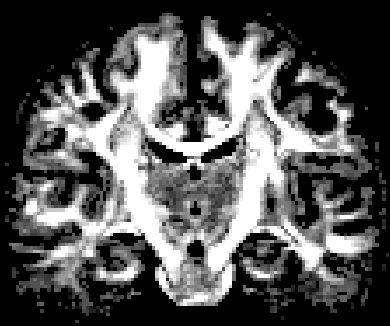

We perform NODDI on the HCP multi-shell data using the released matlab toolbox by the authors (Zhang et al., 2012). The first row in Fig. 11 shows the parameter maps by the NODDI toolbox, i.e., the map and map. It should be noted that is calculated based on and Eq. (7) in the author-released toolbox. Fig. 11 also shows OO and OD from NODDI, based on the closed form in Eq. (13) with a scaled . The scale on is used for a better contrast in the obtained dispersion index map. The obtained map has intensities that are less than in most voxels. Thus, as shown in Fig. 4, obtains the range which is good for , and obtains the range which is good for OD. The two dispersion index maps calculated in two ways from visually have similar contrast.

Non-negative spherical deconvolution (NNSD) (Cheng et al., 2014) is performed to estimate non-negative fiber ODFs from three-shell DWI data. NNSD works for multi-shell data. It is more robust to noise, and the obtained fiber ODFs (fODFs) in isotropic regions are closer to the isotropic spherical PDF, compared with conventional constrained spherical deconvolution (Tournier et al., 2007). After obtaining the fODFs by NNSD, the peaks are detected from the estimated fODFs with GFA larger than , as described in Section 3.4. OO and OD are calculated from the spherical harmonic representation of fODFs along their principal peaks as shown in Algorithm 1. The second row in Fig. 11 demonstrates FA from tensors estimated by DTI, OO and OD from fODFs estimated by NNSD, and the total distortion map estimated from the local orthogonal frames of fODFs. Fig. 12 and 13 show the close-up views of fODFs, local orthogonal frames, and the six proposed indices for the red and blue regions in Fig. 11, where the region shown in 12 is also visualized in the DFA pipeline in Fig. 1. The fODF glyphs are colored by using its sampled directions. The three orientations in the local orthogonal frame in each voxel are visualized by using three tubes in red, green, and blue colors respectively. There is no local orthogonal frame in some voxels because those voxels have GFA values lower than . These figures show the following: 1) OO is high in anisotropic areas with well-aligned directions, while OD is high in isotropic or crossing areas. 2) The four orientational distortion indices are low in areas with well aligned principal directions, and zero in isotropic voxels without peaks. Distortion indices are high in voxels where the principal directions in its local neighborhood change largely. 3) The central voxels in red region is the crossing area of the Corpus Callosum from left to right and Fornix that goes through the coronal slice. The twist index showed high value in this crossing area as expected.